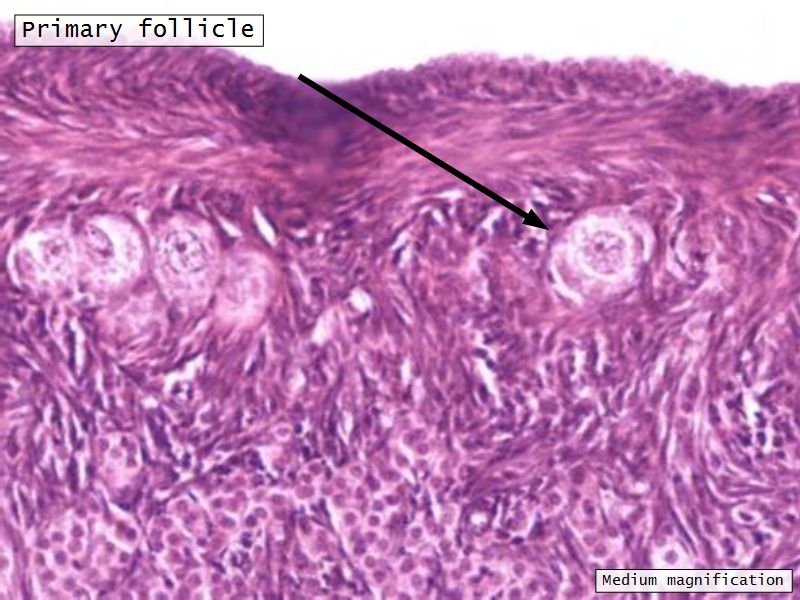

Follicular maturation

- Primordial follicle

- Growing follicle

- Primary follicle

- Secondary follicle

- Mature follicle (Graafian)

Components of a follicle

- Theca

- externa

- interna

- basal lamina

- Granulosa cells

- Antrum

- Cumulus oophorus >> Corona radiata

- Oocyte